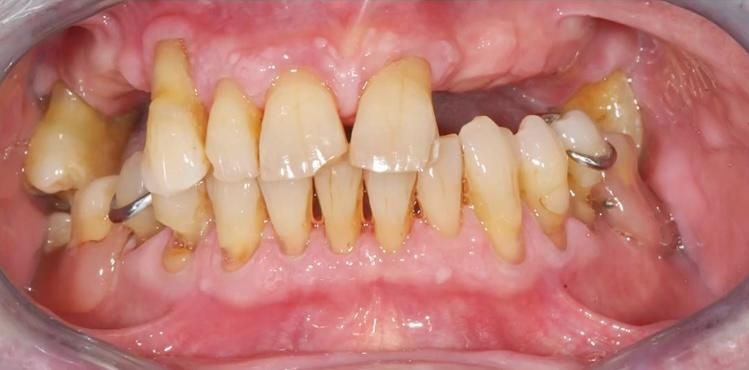

Il nostro fiore all’occhiello, offrire una soluzione moderna e altamente risolutiva nei casi di pazienti edentuli.

Restituire loro una dentatura fissa e naturale affinché con gli impianti si torni a sorridere con ottimi risultati dal punto di vista estetico e funzionale.

Oggi la chirurgia implantare ci permette di tornare a sorridere con la sicurezza di avere denti indistinguibili da quelli naturali e con risultati duraturi nel tempo.